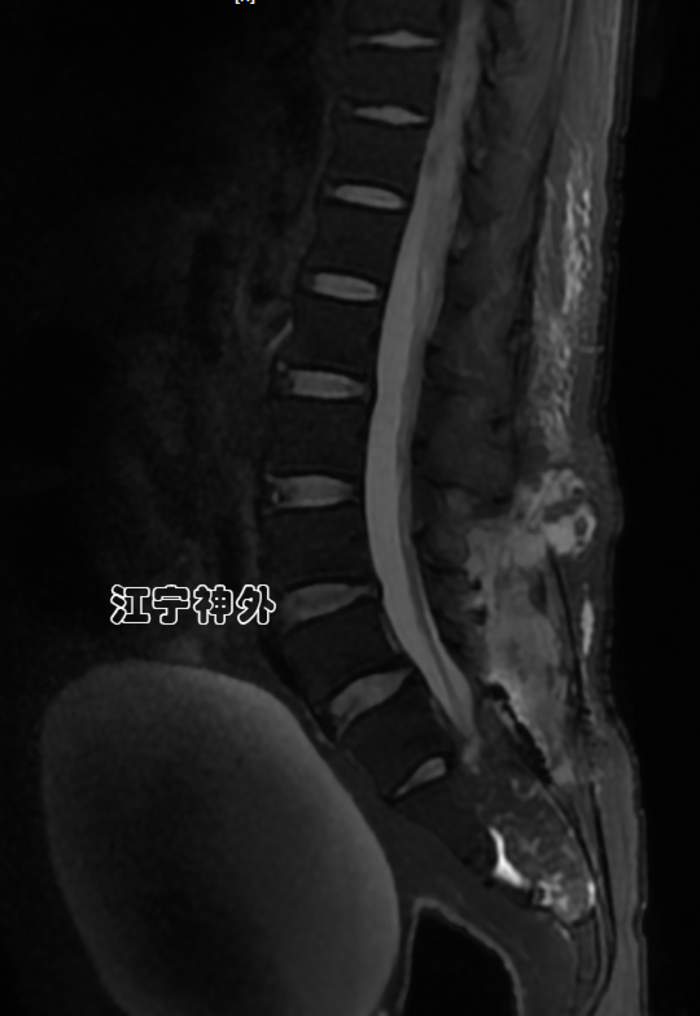

我院术前磁共振检查发现,骶1-3两个巨大骶管囊肿,其中左侧骶管囊肿更大,但症状却是在右侧。

另外,由于巨大骶管囊肿的长期压迫,患者的骶骨已被广泛侵蚀破坏,无论是椎体还是椎板骨质都已大量损失,很多部位已经穿通。

术后磁共振显示双侧骶管囊肿封堵良好。并且使用钛板修补了缺损的骶管后壁,避免骶管内容物膨出。